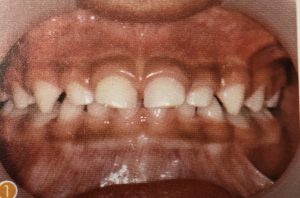

上唇小帯の異常

上唇小帯は、生まれた時は大きく、付着部も歯槽頂近くになりますが、乳歯の萌出に伴い通常は退縮します。

上唇小帯への対応

上唇小帯は出生児には大きく、付着部も歯槽上部の近くになりますが、乳歯の萌出に伴い、通常は退縮します。乳歯列が完成する時期を過ぎても、上唇小帯の肥厚や付着異常により乳中切歯間に隙間が認められる場合は、6から7歳の永久歯放出後に改めて診断し、上唇小帯の切除の判断をします。上唇小帯が歯冠側に付着している場合は上唇の伸展や運動が阻害されるため、口唇の閉鎖不全を引き起こすことがあります。